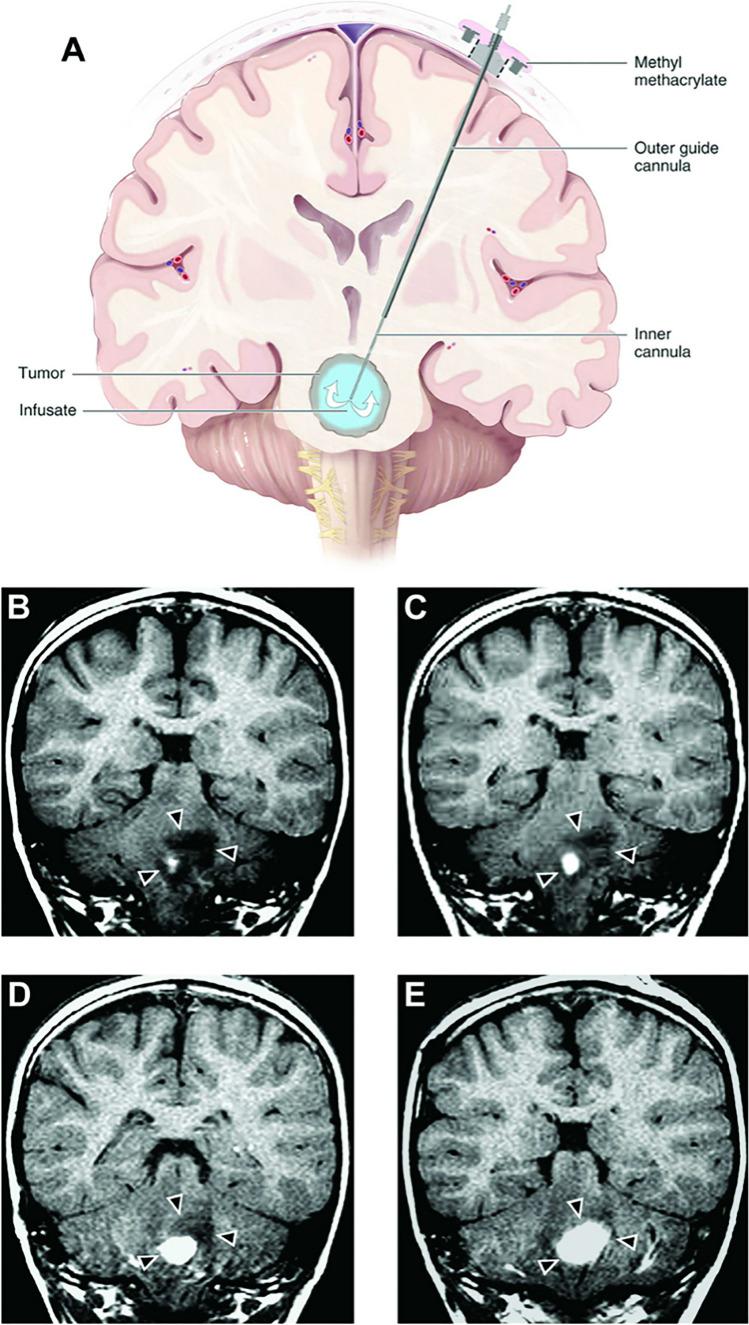

Adjuvant convection-enhanced delivery for the treatment of brain tumors.

Malignant gliomas are a therapeutic challenge and remain nearly uniformly fatal. While new targeted chemotherapeutic agentsagainst malignant glioma have been developed in vitro, these putative therapeutics have not been translated into successful clinical treatments. The lack of clinical effectiveness can be the result of ineffective biologic strategies, heterogeneous tumor targets and/or the result of poortherapeutic distribution to malignant glioma cells using conventional nervous system delivery modalities (intravascular, cerebrospinal fluid and/orpolymer implantation), and/or ineffective biologic strategies.

We describe the properties, features and landmark clinical trials associated with convection-enhanced delivery for malignant gliomas.We also discuss future trends that will be vital to CED innovation and improvement.

Efficacy of CED for malignant glioma to date has been mixed, but improvements in technology and therapeutic agents arepromising.